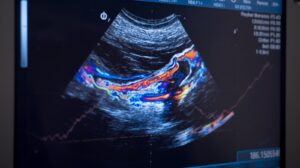

فحص الدوبلر هو تقنية متطورة من السونار تستخدم موجات صوتية عالية التردد لتقييم حركة الدم داخل الأوعية الدموية. يسمح هذا الفحص للطبيب بمعرفة ما إذا كان هناك انسداد، ضيق، تجلط، أو ضعف في تدفق الدم.

- تقييم سرعة واتجاه تدفق الدم داخل الشرايين والأوردة.